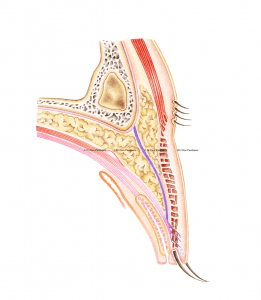

The most commonly performed eyelid surgery in people from East Asia is sometimes referred to as “double eyelid surgery”, and is a cosmetic surgical method that reconstructs the skin of the upper eyelid. Often oculoplastic surgeons also partially remove any skin surplus, which is a natural consequence of ageing. We oculoplastic surgeons can also create an eyelid crease – something that is naturally missing in people from East Asia (which is sometimes referred to as a “mono-lid”).

It is important that the doctor performing this procedure has special expertise in this area. Oculoplastic surgeons are ophthalmologists who specialize in eyelid surgery and who – like no other – understand the complex relationship between the eye and the eyelid. For example, an assessment of the different aspects of the eyelid such as eyelid height (the position of the lash line relative to the pupil), the amount of skin, the presence or absence of a so-called eyelid crease (the line above which the skin fold forms), the shape of the epicanthal fold, and the position and shape of the eyebrow should all be made preoperatively. It is also important to look for signs of dry (or wet) eyes, as this helps to prevent eye complaints after the procedure.